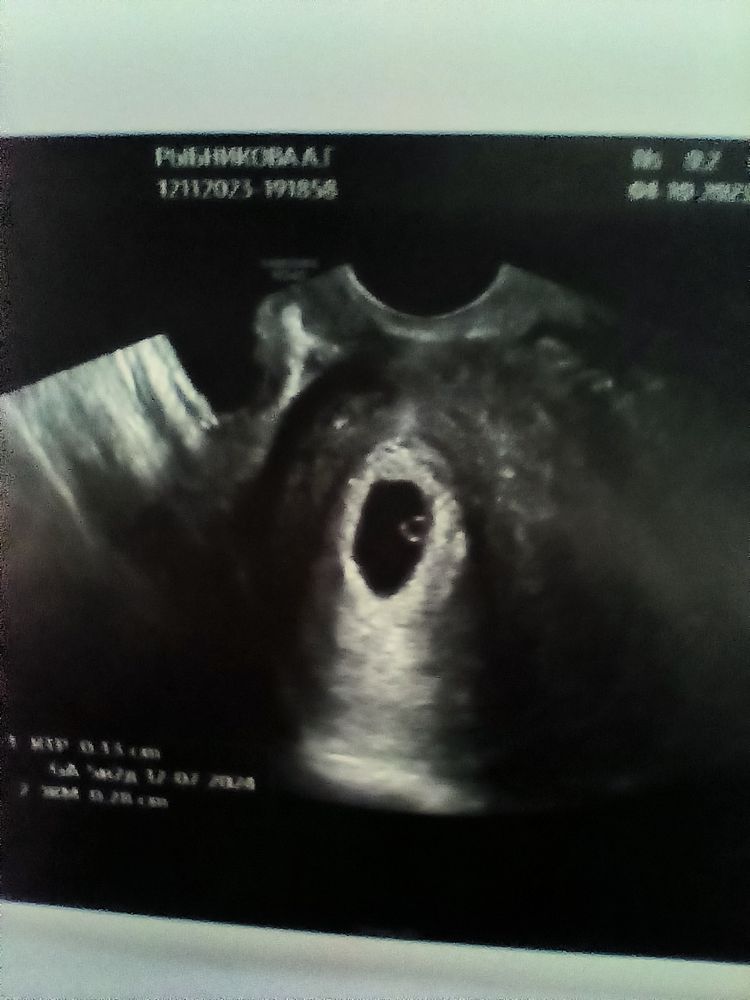

Уже появился эмбриончик🩷

ириска, да , ктр 1.3 мм, жм -2.8 мм, хорион кольцевидный 5.5 мм, сказали вроде все в норме, соответствует сроку